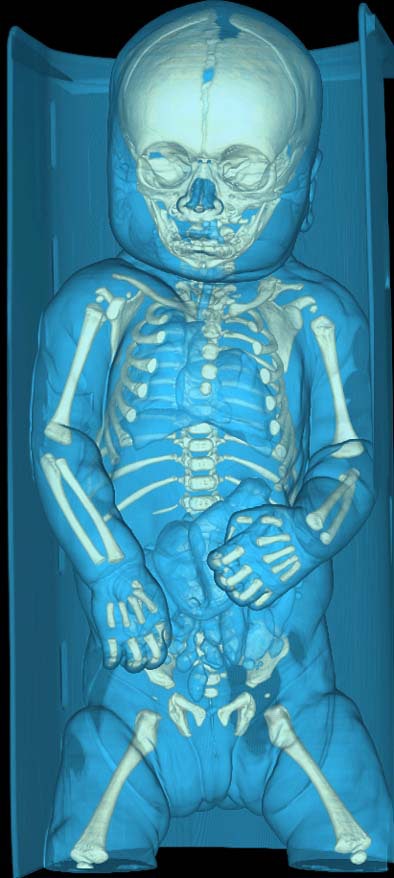

Virtual autopsy often works where traditional autopsy fails, Persson said, offering an example from his institute, which investigated the case of a 3-week-old infant who had died mysteriously in the operating room during a standard laryngoscopy.

"The autopsy couldn't find the cause of death," he said. But CT showed "a very tiny hole," in the heart, the result of an iatrogenic injury during the procedure.

![]() |

| A 3-week-old infant (above) died mysteriously following laryngoscopy, and traditional autopsy was inconclusive. However, CT showed the cause of death to be a puncture wound to the heart evidenced by an air pocket in the organ (below), which resulted from an iatrogenic injury during the laryngoscopy procedure. Images courtesy of Dr. Anders Persson and Patric Ljung. |